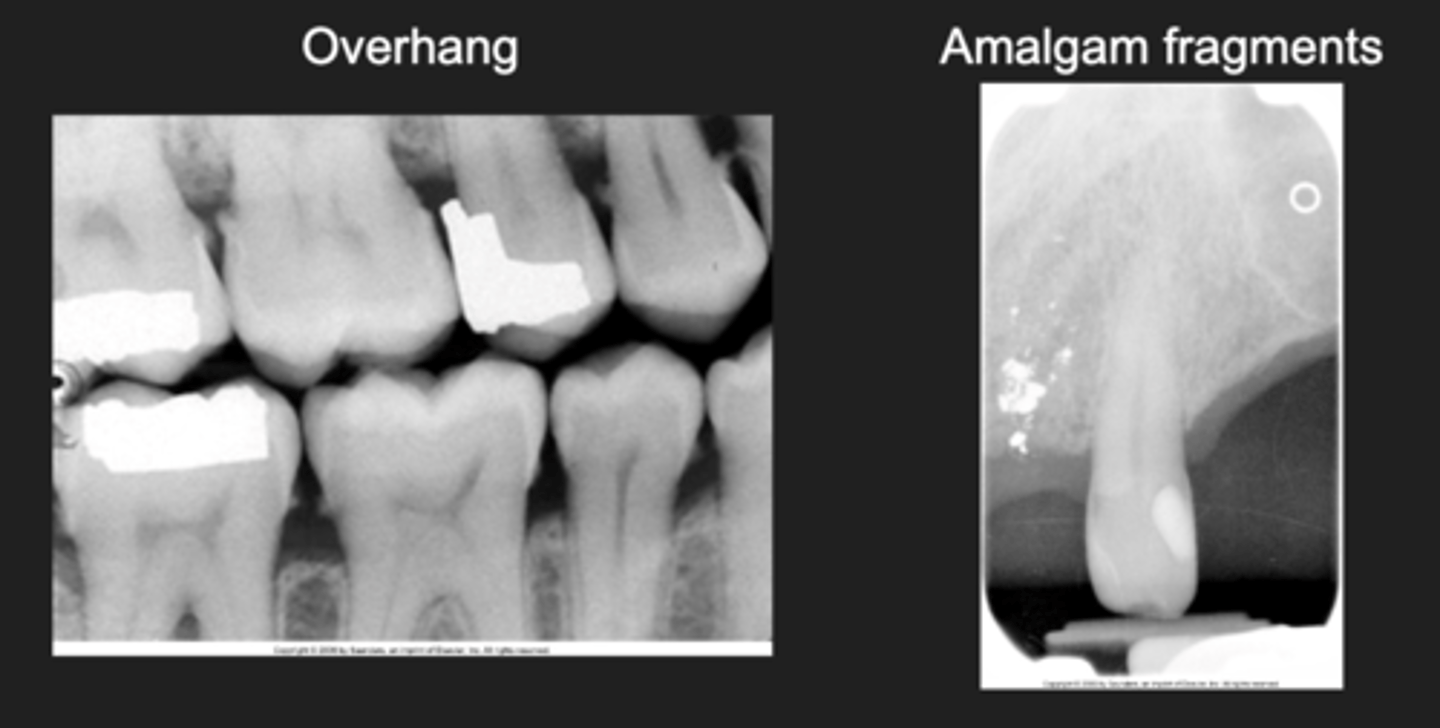

- Overhangs

- Amalgam fragments

Amalgam examples

- Overhang and amalgam fragments